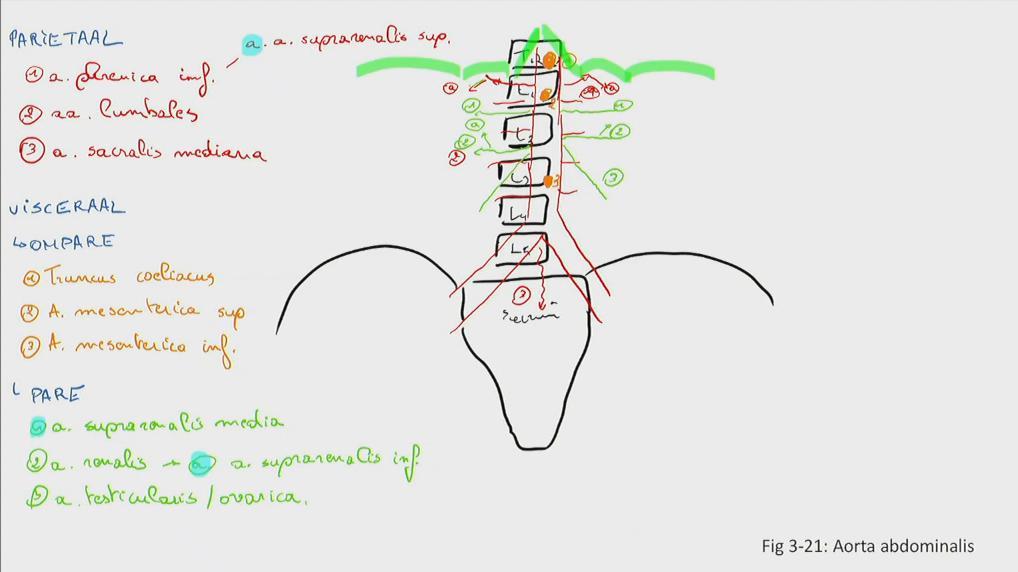

Fig 3.21: Aorta abdominalis

|